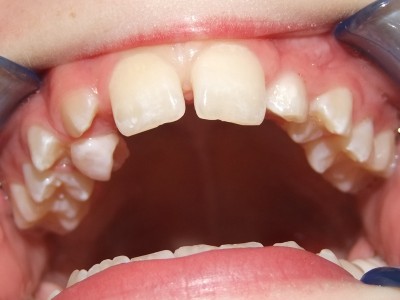

Leeftijd bij aanvang: 10 jaar

Voor behandeling